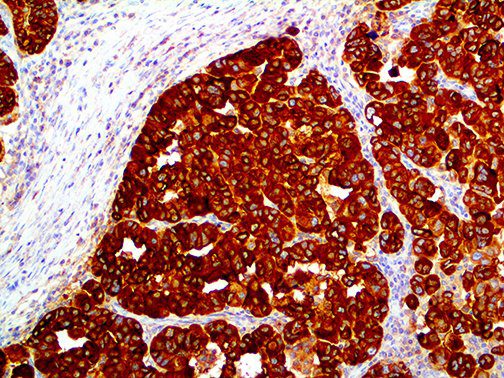

It is the ICU physician who is most likely to witness one of the deadliest manifestations of the abnormal immunological response, the cytokine storm syndrome (CSS). This response is also referred to by some as the cytokine release syndrome (CRS). CSS is characterized by continuous activation and expansion of macrophage and lymphocyte populations, which secrete large amounts of cytokines, causing the cytokine storm. This massive cytokine release is akin to hemophagocytic lymphohistiocytosis (HLH) disease, a syndrome characterized by initial unchecked and persistent activation of cytotoxic T lymphocytes and NK cells.